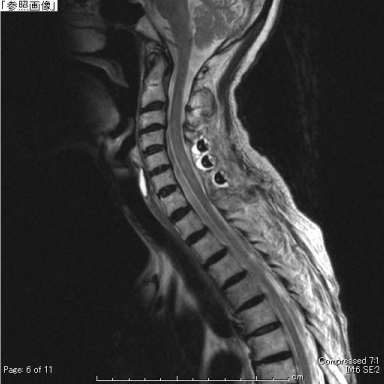

One day after tPA administration, the patient developed left hypoalgesia in the area innervated by T1–T4. She could not sense urination, contract the anal sphincter, or grasp her right hand. Cervical spine MRI performed two days after symptom onset showed right-sided cervical SEH from C4–Th5. The patient was immediately transferred to our department. Manual muscle test scores were 0 for the right upper and lower limb muscles, except the deltoid and elbow flexors. The hematoma was immediately removed via laminoplasty. Postoperatively, the muscle strength gradually recovered. At 2 years postoperatively, the manual muscle test scores for the right upper and lower limb muscles were all 5, and the grip power was 5 kg on the right and 16 kg on the left; the only sensory disturbance was a burning sensation in the right hand.

Figure 2. Preoperative MRI showing a heterogeneous extradural mass from the level of C5 to T5. The spinal cord is compressed by the extradural mass. A: T2-weighted sagittal image, B: T2-weighted transverse image at the level of C5